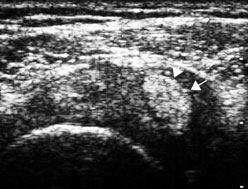

Ακτινογραφία που δείχνει τις άγκυρες μετά από

την αποκατάσταση μιας βλάβης Bankart

Μαγνιτική τομογραφία μιας βλάβης SLAP